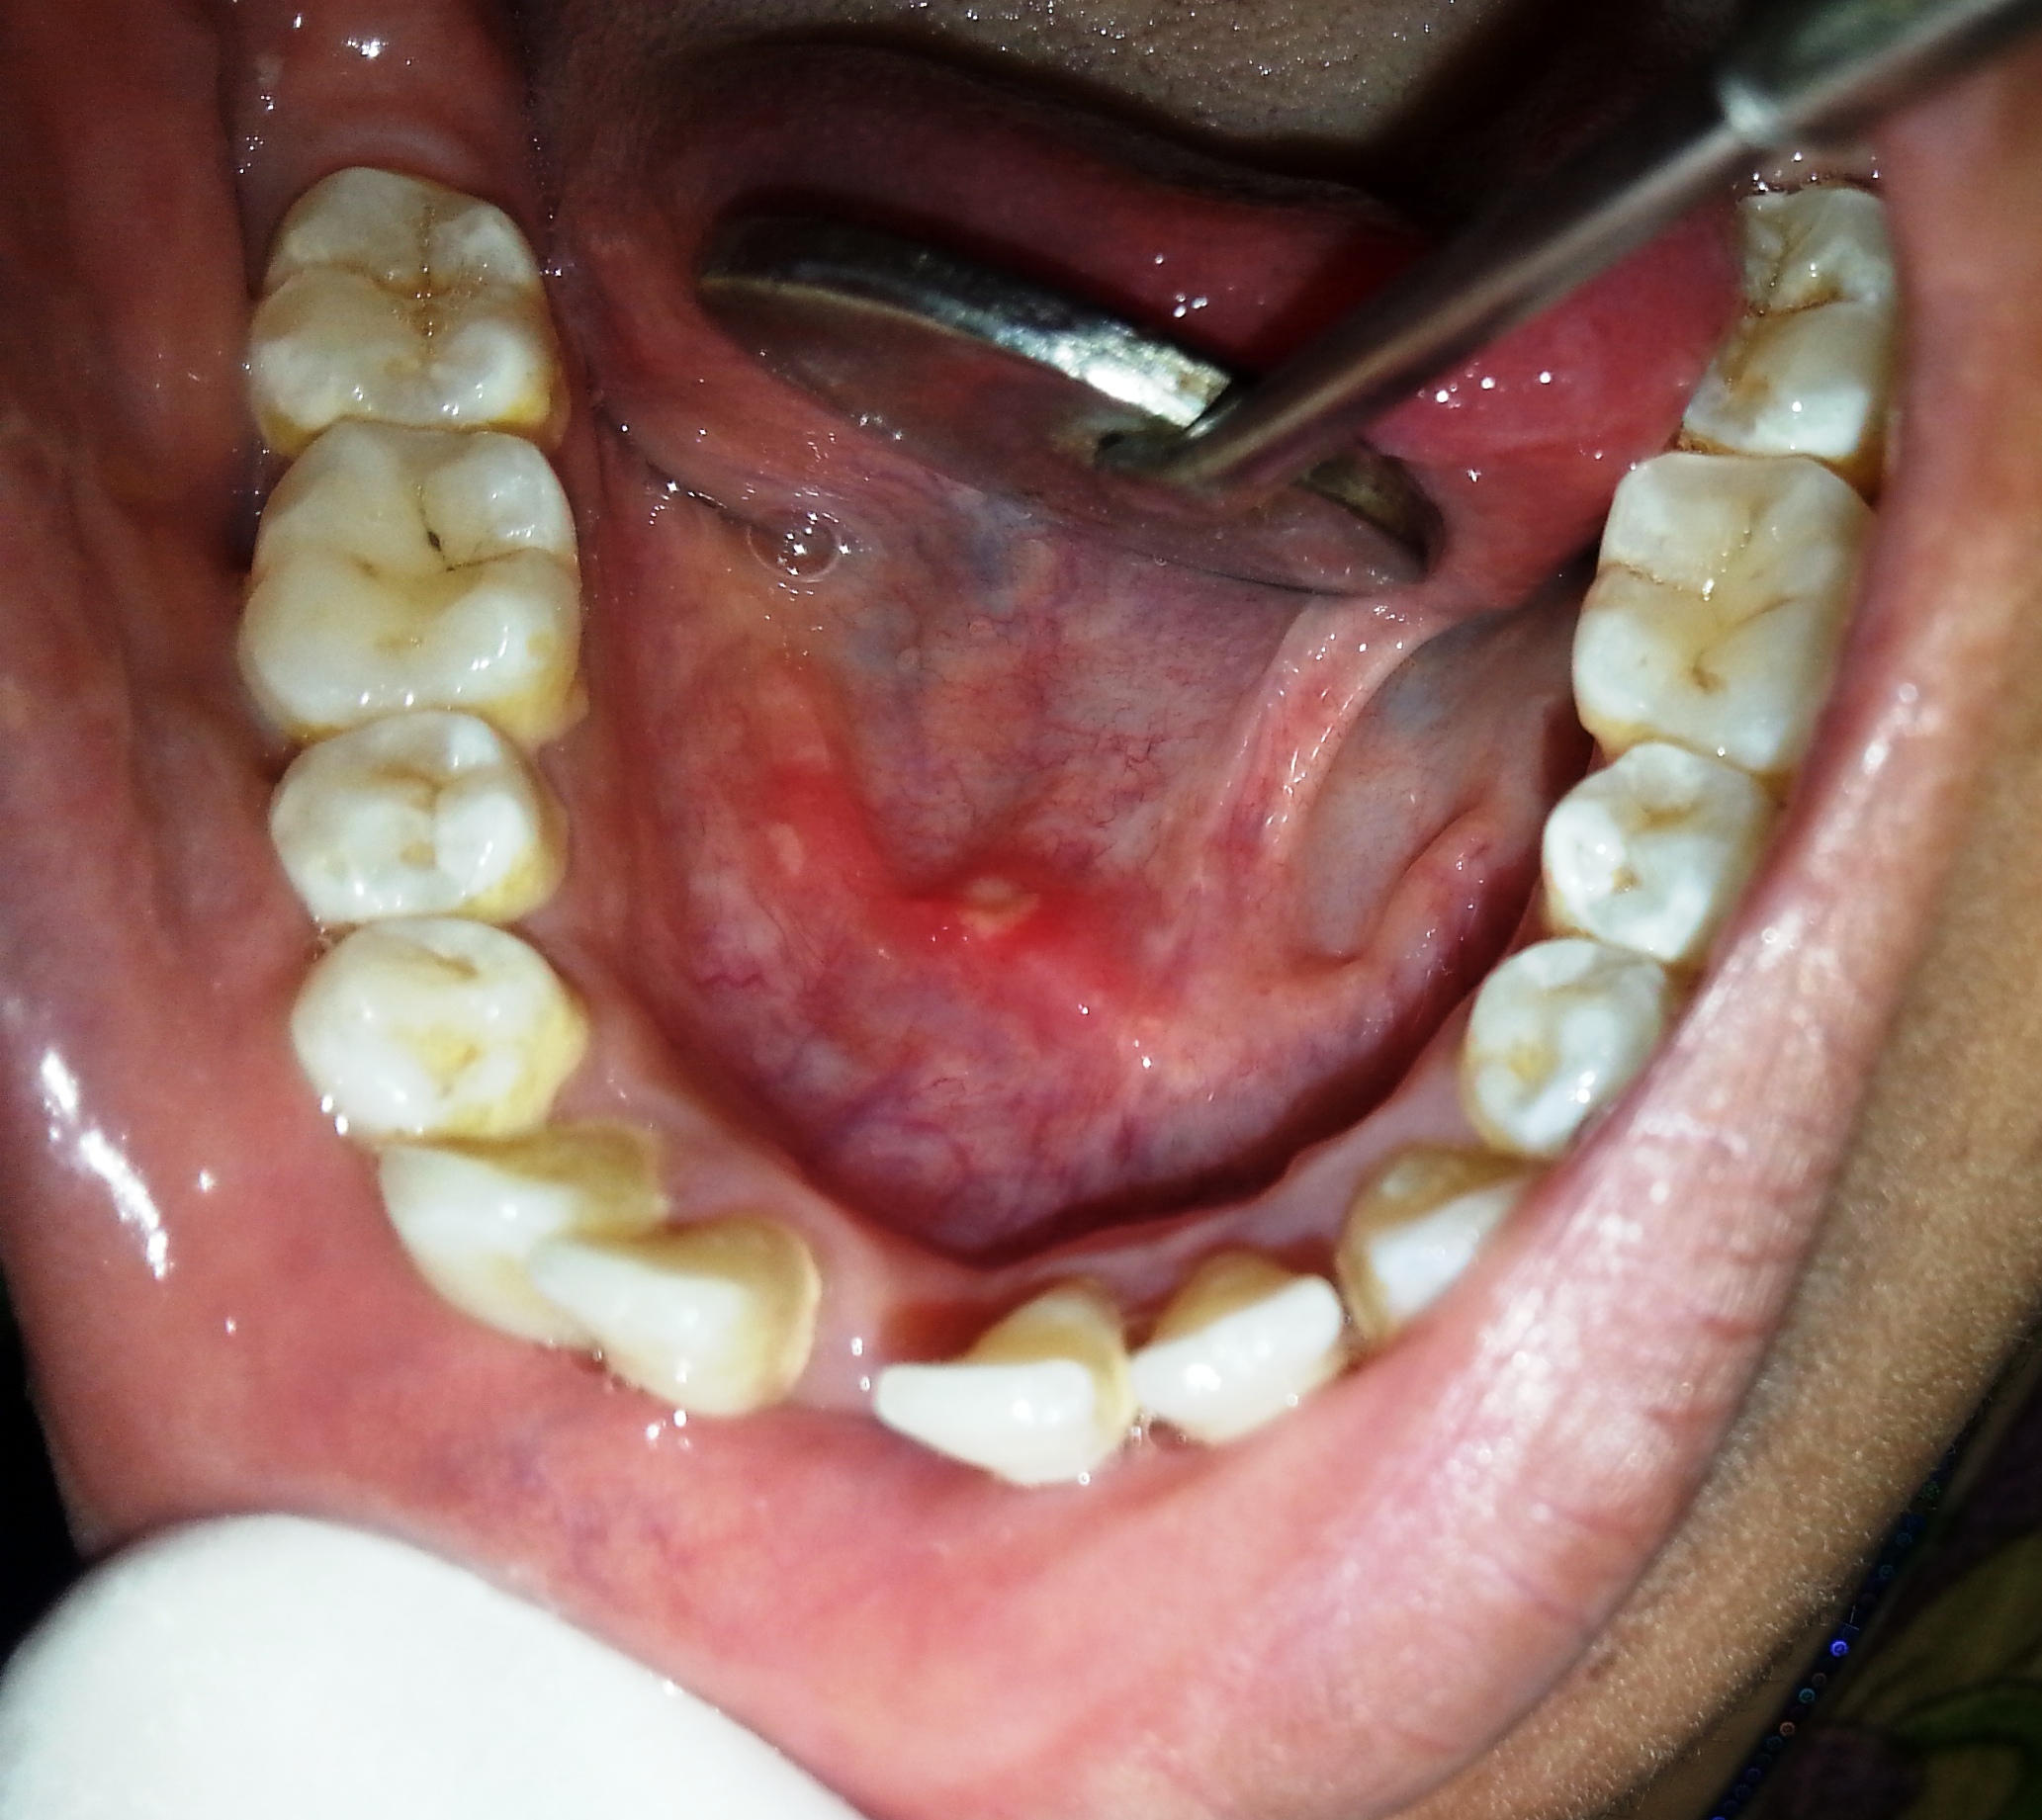

aphthous ulcers

Oral precancers are usually asymptomatic and painless so the patient is unaware of the lesions presence.